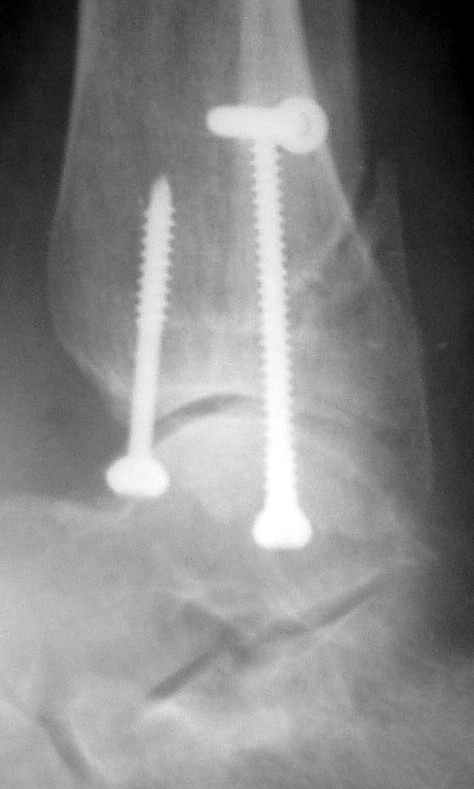

Ниже рентгенограммы

До операции 28 июля

Операция 29 июля

Через месяц

Боковой через месяц

15 ноября прямой

15 ноября боковой

15 ноября трехчетвертной

12 января прямой

12 января боковой

12 января трехчетвертной

Риторический вопрос - в каком руководстве рекомендован такой способ остеосинтеза наружной лодыжки?

Очевидно, такой результат операции был запрограммирован. При невосстановленной длине и практически нефиксированной малоберцовой кости (этот кортикальный винт - как карандаш в стакане), при неустраненном подвывихе, невправленной и тоже нефиксированной внутренней лодыжке нет стабильной вилки сустава. Если такую операцию сделать даже сразу, а не через 4 месяца, то результат ожидаем

тот же.

Если до сих ничего не сделано, с артродезом сустава в данный момент я бы повременил, на выставленных январских снимках хорошо сохранившийся сустав, а в "мортиз" (трехчетвертной) и на боковых снимках не менее 5 мм укорочение малоберцовой кости. Косые переломы лучше фиксировать пластинами, как то мы разбирали случай, где было отмечено, что это закон "таранная кость всегда следует за малоберцовой".

С подобным случаем приходилось сталкиваться у гормонозависимого пациента с 4 месячным подобным переломом после безуспешного лечения в аппарате Илизарова. Вальгусная стопа, остеопороз, диастаз в медиальной лодыжке. Произвел открытую репозицию мед лодыжки, синтез тяговым винтом 3.5 мм из титана, костную пластику спонгиозой, до 2 см куб из надлодыжечной зоны. Затем остеотомия по линии перелома малоберцовой кости узким долотом из 0.5 см доступа и ручная коррекция вальгуса . Блокирующий винт через обе кости. Остеосинтез по MIPO технологии пластиной 1-3 трубки. Внешней фиксации не применялось, перелом сросся за три месяца. Согласен с д-ром Кульжановым, без пластины в подобных случаях не обойтись.